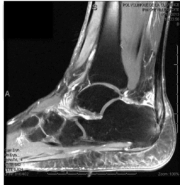

Deux mécanismes principaux sont décrits :

- le conflit de Haglund : une proéminence osseuse du calcanéum frotte contre le tendon et crée une inflammation,

- la forme dégénérative : le tendon s’use progressivement, parfois avec des dépôts calcifiés (enthésophytes). Souvent, ces deux mécanismes se combinent.

Imagerie